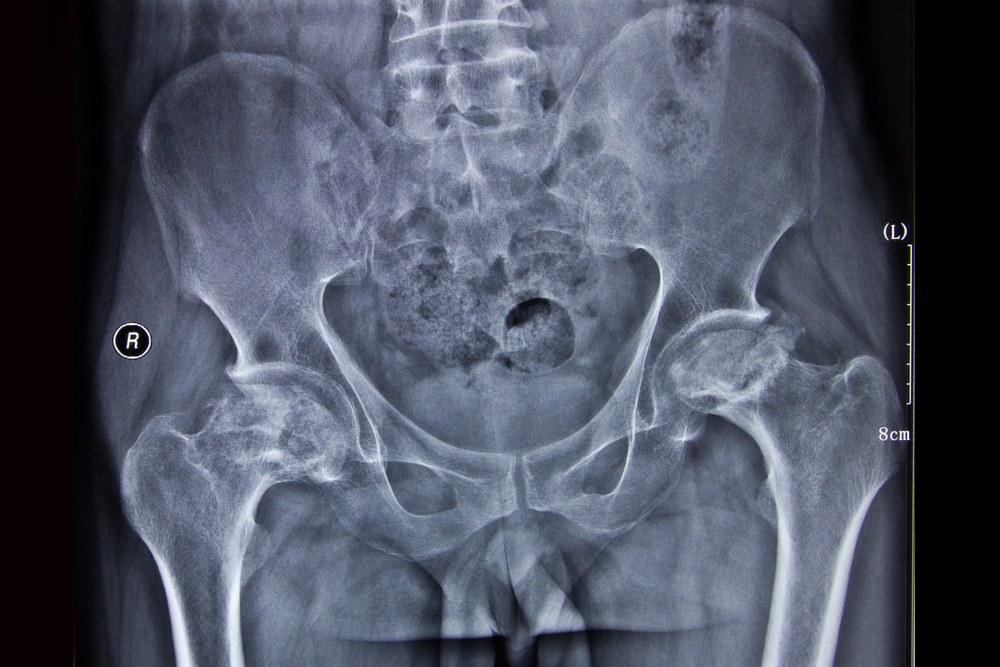

Наиболее распространенным и доступным практически каждому ЛПУ методом диагностики является рентгенография пораженного тазобедренного сустава. Она позволяет верифицировать АНГБК III и IV стадий, однако при более ранних стадиях изменения на рентгенограмме отсутствуют.

К сожалению, в силу небольшой информированности многих докторов о данной патологии, не обнаружив патологических изменений на рентгенограмме, больному выставляют диагноз «остеохондроз» или подобные ему, а каждый третий пациент и вовсе остается без диагноза. Это неверная тактика. В такой ситуации, когда у пациента имеются симптомы асептического некроза, но рентгенограмма показывает, что патология отсутствует, пациент нуждается в расширенном обследовании более информативными методами визуализации – в проведении компьютерной или магнитно-резонансной томографии.